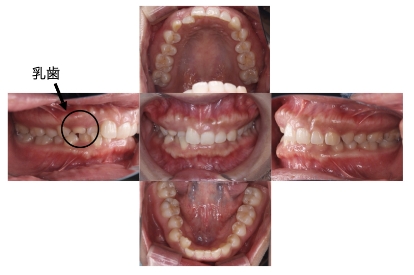

BEFORE

AFTER

症例12

上顎前突、叢生

抜歯

ブラケット矯正

上下顎叢生(上下の前歯のガタガタ)および上顎前突のケースです。

装置はラビアル(上下表側)で、左上C(乳歯)と右上および下顎両側の小臼歯を抜歯(計4本)を行っています。抜歯したスペースを利用し、上下の前歯の後方移動と叢生(ガタガタ)の改善を行っています。また、上顎前突改善のため歯科用アンカースクリューを使用し、上顎歯列全体の後方移動をおこないました。

主訴 上下の前歯のガタガタと出っ歯を治したい。

年齢・性別 16歳 男性

お住まいの地域 神奈川県川崎市

治療方針 抜歯スペースを利用して上下前歯の叢生(ガタガタ)の改善、上顎歯列の遠心移動

抜歯部位 上顎右側第一小臼歯、上顎左側乳犬歯、下顎両側第一小臼歯

使用装置 ラビアル(上下表側)、顎間ゴム、歯科用アンカースクリュー

治療期間 2年8か月

治療回数 21回

リテーナー クリアリテーナー